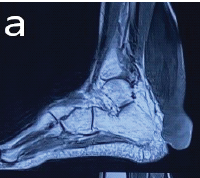

We are presenting 35-years-old free medically, active soldier referred to the orthopedic clinic from family medicine after noticing abnormal incidental findings on X-rays (Fig. 1-4).

On inquiring him, he doesn’t recall any problem during his childhood and performing his military duties. On clinical examination of the patient, he had characteristic features of patellar absence with prominent femoral condyles and hollow sulcus as per computed tomography (CT) both knees (Fig. 5,6).